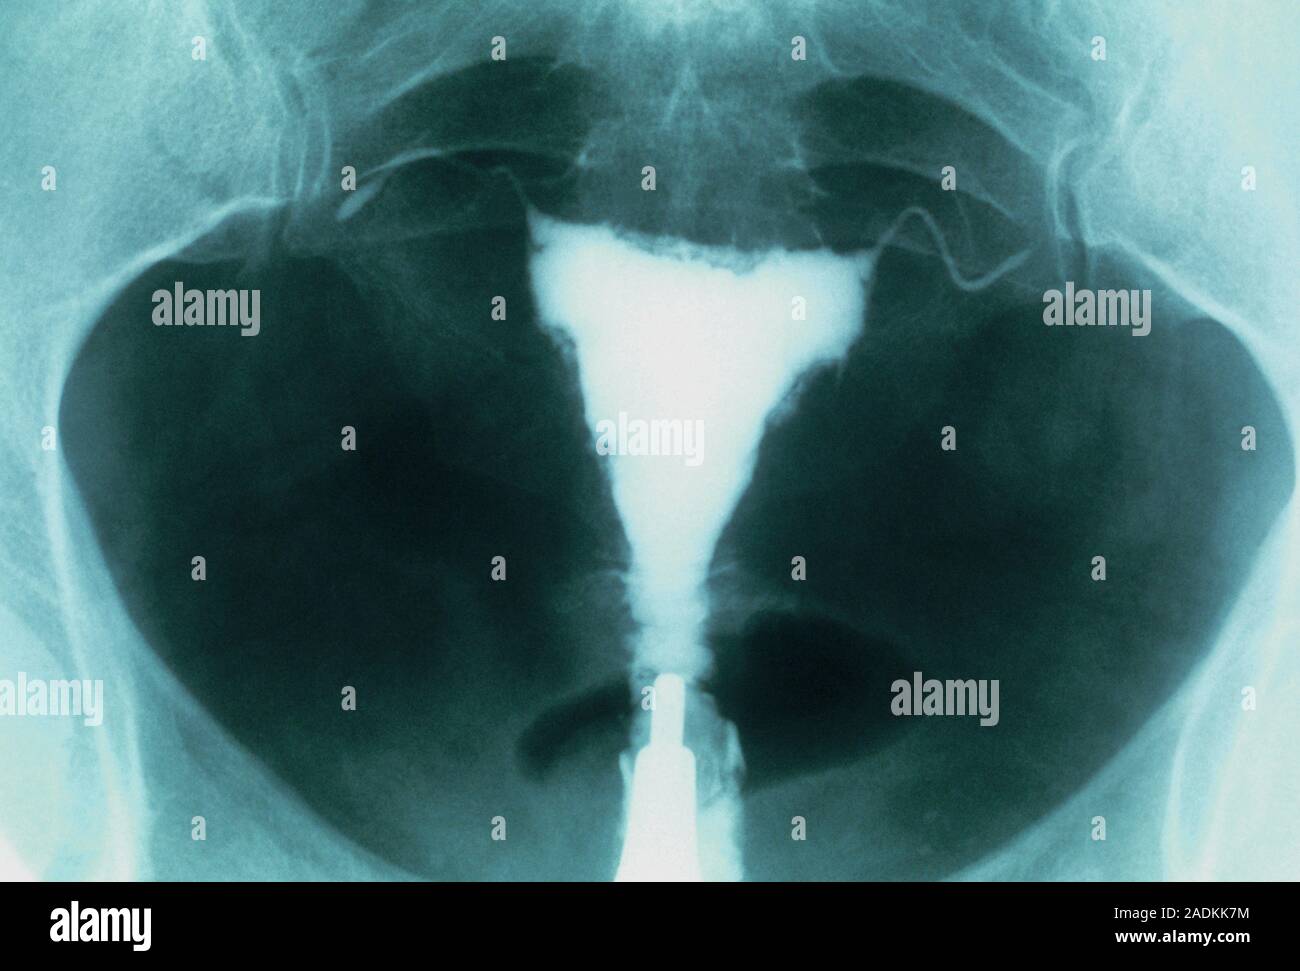

From www.alamy.com

Postmenopausal uterus. Xray of the uterus (white, centre) of a post Thickened Uterine Lining Postmenopausal The most concerning is cancer which can appear as thickening of the. In a postmenopausal woman with vaginal bleeding, the risk of cancer is approximately 7.3% if her endometrium is thick (> 5 mm) and < 0.07% if her. A thickened endometrium in a post menopausal patient can be due to a variety of causes. Abnormal endometrial lining thickness, along. Thickened Uterine Lining Postmenopausal.